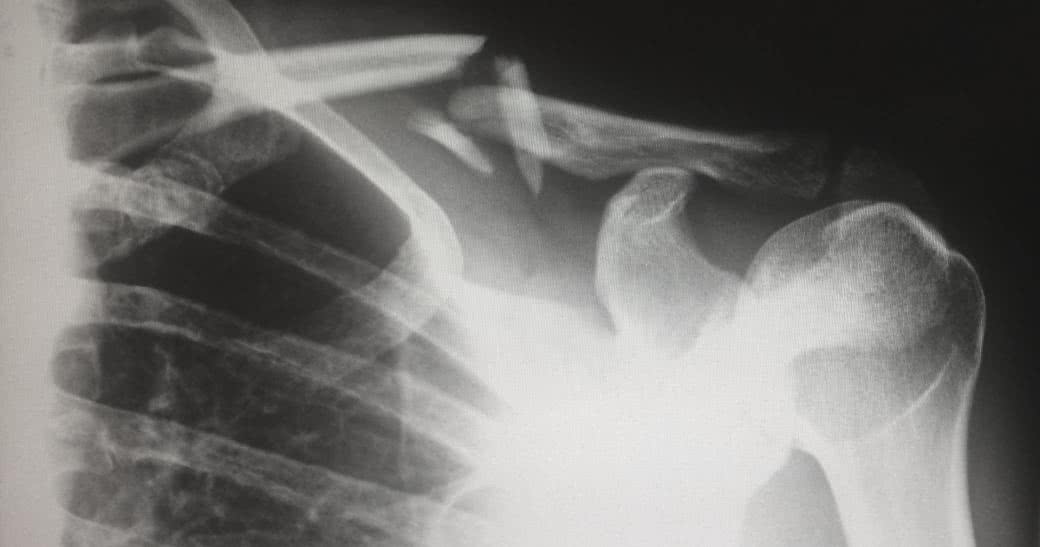

Wyniki norweskich badań Nord-Trondelag Health Survey wykazały również znamiennie większe ryzyko złamania szyjki kości udowej u kobiet z cukrzycą, przy czym podstawowe znaczenie miał dłuższy niż 5 lat okres trwania choroby. Dopiero po tym czasie masa kostna osiągała u nich znacznie niższe wartości. W innym badaniu prawdopodobieństwo przebycia złamania przez kobietę z cukrzycą typu 1 było nawet 25 razy większe niż w populacji ogólnej15.

Tyroksyna skraca cykl przebudowy kości z 200 do 113 dni, powodując niedostateczne jej odtworzenie po resorpcji (w tym zmniejszenie grubości i zaburzenie struktury). Potwierdzają to badania, w których stwierdza się redukcję gęstości kości u kobiet z chorobą Gravesa-Basedowa w obrębie szyjki udowej (o 10%) i kręgosłupa (12%)9. Co więcej, ciężka nieleczona nadczynność tarczycy może prowadzić do przyspieszonego ubytku masy kostnej, łagodnej hiperkalcemii i wzrostu nerkowej utraty wapnia i obniżenia poziomu czynnego metabolitu witaminy D3. I chociaż w większości przypadków zmiany są odwracalne (przy skutecznym leczeniu nadczynności możliwy jest znaczący wzrost gęstości kości, choć nie zawsze osiągnie on wartości prawidłowe), biomechaniczne zmiany mogą powodować, że będą one mniej wytrzymałe na urazy, a tym samym - bardziej podatne na złamania10.